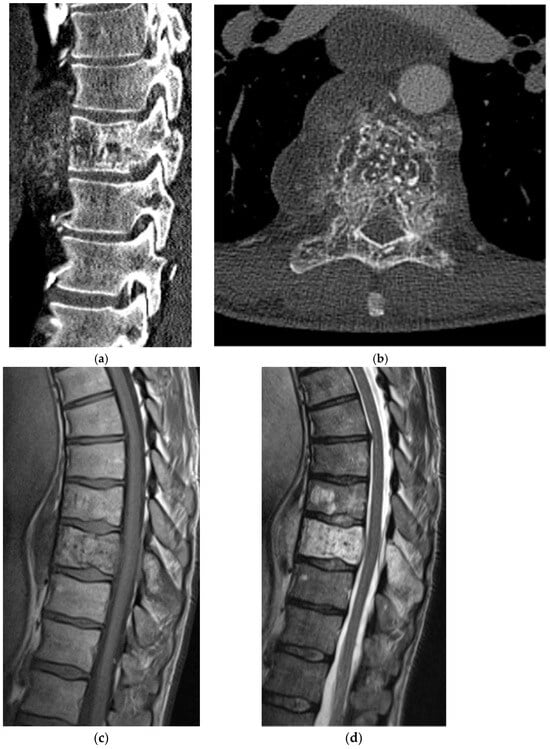

2.5.2. Aneurysmal Bone Cyst

2.6. Fibro-Osseous